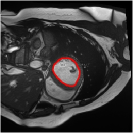

4.4 Comparison with cardic MR images for left ventricle segmentation

In this section, we continue to conduct experiments on cardiac MR images. However, we focus on the right ventricle, which is equally important as the left ventricle in cardiac MR diagnoses. In the near short-axis view, the left ventricle has a crescent shape, while the right ventricle is closer to circular. This does not imply that the right ventricle is easier to segment; in the MR images we use, the right ventricle often shows low-signal-intensity shadows, which may be caused by the imaging characteristics of certain tissues or fluids, leading to interference in segmentation. Moreover, there is a layer of myocardial tissue surrounding the right ventricle that overlaps with the boundary of the right ventricle, posing challenges for accurate identification.

Fig. 8 presents the segmentation results of the right ventricle from the DRLSE-ADMM [WALI2023109105], ABC model [WENG2021115633], RESLS [8765635], the RefLSM, and the ground truth. The results from the DRLSE-ADMM model in the 1st row reveal severe local minima due to low-signal-intensity shadows in the right ventricle. Additionally, both the ABC and RESLS models fail to correctly identify the right ventricle boundary because of the interference from surrounding myocardial tissue, as seen in the 1st and 3rd columns of Fig.8. In comparison, the proposed model gets more satisfactory segmentation results that are closer to the ground truth. Similarly, we evaluate the segmentation performance of all models by calculating the Dice and Precision values and drawing Fig. 9. This overlay plot presents the best, median and worst segmentation results, along with the overall range of outcomes that it is clear that the proposed model segments the right ventricle with greater accuracy than the other models and performs well in different images.